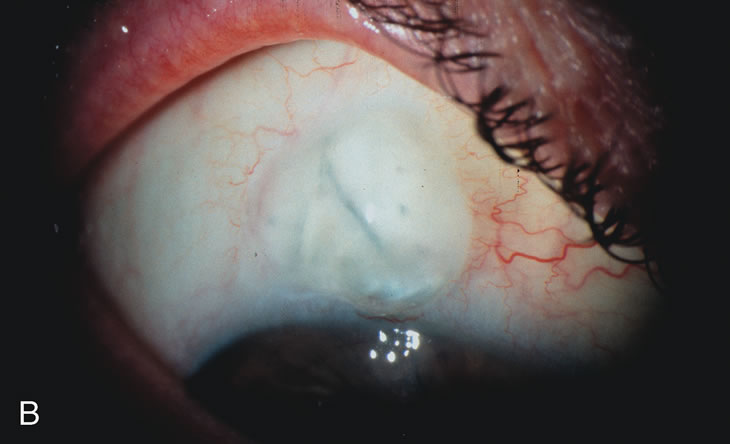

CATARACT EXTRACTION CAUSES PARTIAL OR COMPLETE FAILURE OF EXISTING FILTERING BLEBS

Cataract extraction by any technique performed in a patient with a pre-existing filter will have an effect on the previous filtering bleb.121–124 Bleb failure is more likely with ECCE compared with small-incision phacoemulsification.125 However, even patients undergoing topical anesthesia with clear corneal phacoemulsification and foldable IOL may experience bleb failure. One of three patients with a functioning filter and preoperative mean IOP of 12 mm Hg without antiglaucoma medications experiences bleb failure after lens extraction (Table 2). These patients require long-term drug therapy or bleb needling to control IOP. 126 Additional incisional glaucoma surgery may eventually be required in up to 10% of patients.127 Intraoperative iris manipulation may cause significant breakdown of the blood–aqueous barrier, resulting in inflammation that causes bleb failure. Even after uncomplicated clear corneal phacoemulsification, IOP may increase an average of 2 to 3 mm Hg due to bleb fibrosis.128 Approximately 20% of filtered patients require a long-term increase in glaucoma medications following uncomplicated clear corneal phacoemulsification with a foldable copolymer acrylic IOL129 (Fig. 3). In situations in which the bleb is not working at all, the eye will have a postoperative pressure spike that mimics that in the patient not having had a prior filtering procedure. In situations in which the bleb is marginal, the pressure spikes tend to be lower, and the final postoperative IOP tends to be around 50% higher than it was preoperatively. These patients require combined procedures in order to reestablish long-term filtration. In situations in which the bleb is very thin, polycystic, and associated with an IOP around 5 to 8 mm Hg on no antiglaucoma therapy; uncomplicated cataract extraction will have a minimal effect on the level of IOP. Patients with functioning glaucoma drainage implants usually have minimal long-term changes in IOP after uncomplicated cataract extraction.130

Fig. 3. Partial bleb failure following clear corneal phacoemulsification with foldable IOL. A. Preoperative bleb appearance prior to temporal lens extraction. Preoperative IOP was 12 mm Hg on no antiglaucoma medications. Time from 5-FU trabeculectomy surgery to lens extraction was one year. B. Bleb appearance 2 months after clear corneal cataract surgery with topical anesthesia. Following lens extraction, increased vascularity was noted along with decreased size of the filtering bleb. IOP increased to 20 mm Hg as early as 2 weeks after surgery, necessitating topical antiglaucoma therapy. C. High magnification view of bleb before lens extraction demonstrates diffuse pale bleb. D. High magnification view of bleb 2 months after surgery. There are vessels surrounding the nasal side of the bleb and the overall bleb size is smaller.